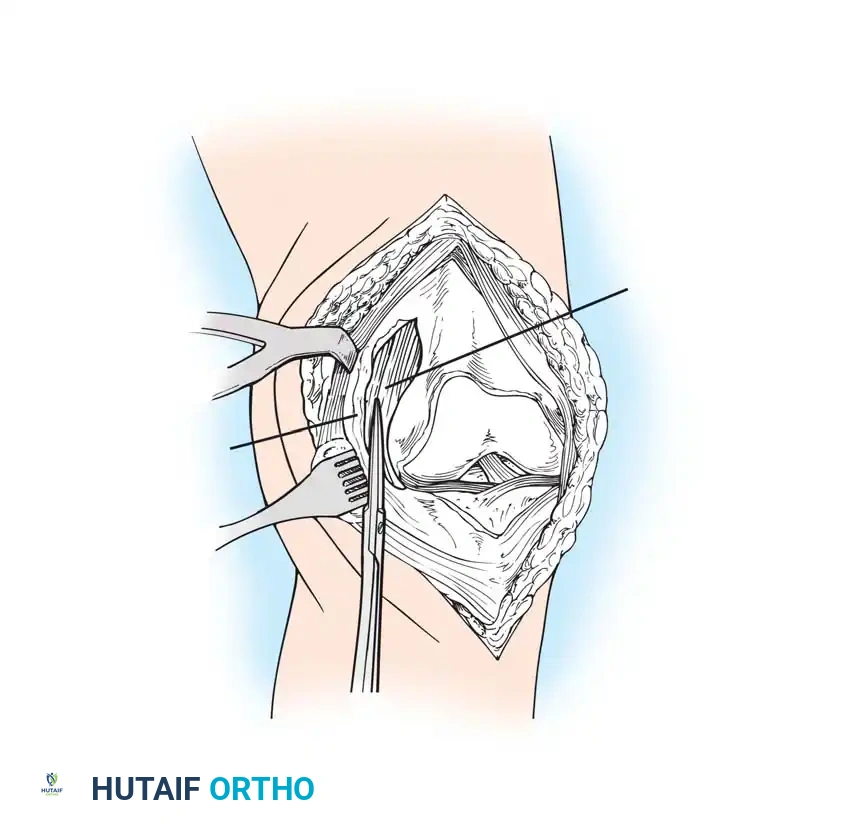

The Subvastus ("Southern") Approach

In an effort to reduce patellofemoral complications and expedite the return of quadriceps function, alternative methods of exposure have been developed. The subvastus approach, advocated by Hofmann, Plaster, and Murdock, avoids violating the extensor mechanism.

- The same anterior midline skin incision is used.

- The proximal retinacular incision is performed by incising the superficial fascia overlying the vastus medialis.

- Bluntly mobilize the distal medial border of the vastus medialis posteriorly to the medial intermuscular septum.

- Lift the origin of the vastus medialis off the medial intermuscular septum to approximately 10 cm proximal to the adductor tubercle, staying distal to the aperture for the femoral vessels.

- Incise the synovium and dislocate the entire extensor mechanism laterally.

Advocates of the subvastus approach note that leaving the extensor mechanism intact results in a more rapid return of quadriceps strength, preserves the vascularity to the patella (specifically the supreme genicular artery), decreases postoperative pain, and reduces the need for lateral retinacular release. However, exposure can be severely limited in obese patients, highly muscular individuals, or those with previous knee surgeries.